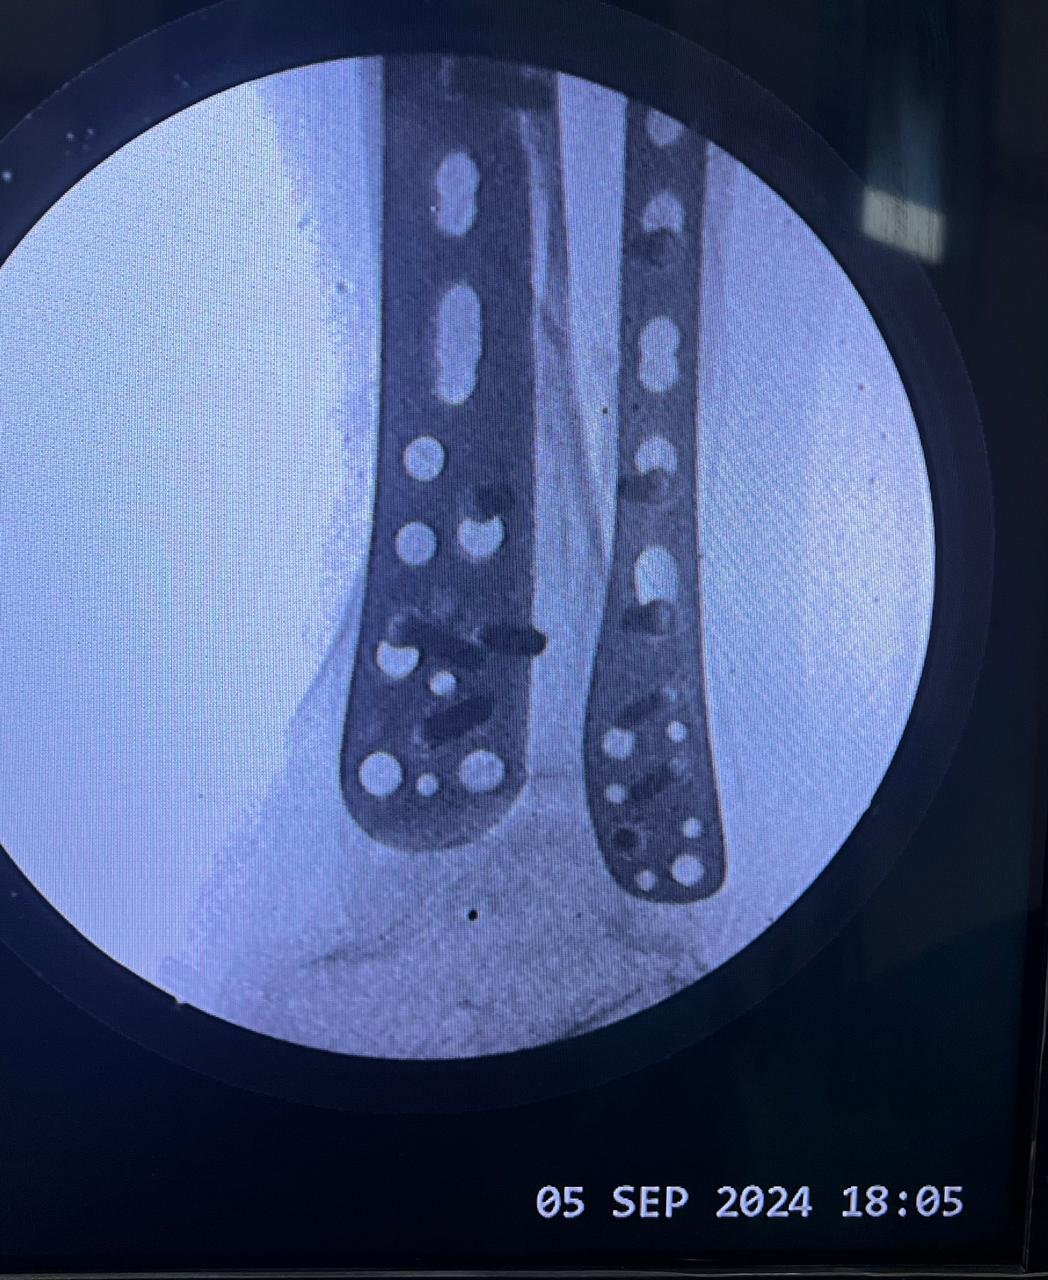

Pre op & postop X-ray compound fracture lower tibia

& fibula | Heal fracture pre & postop | Clavicle